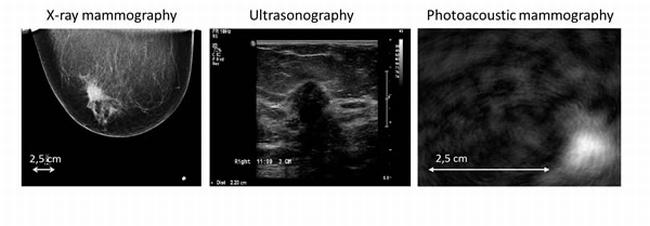

| Diagnostic images of a mixed infiltrating lobular and ductal carcinoma in the right breast of a 57-year-old patient, obtained by x-ray mammogram (left), ultrasonography (middle) and photoacoustic mammography (right). The PA imaging sowed a confined high-contrast abnormality with a contrast in excess of 5 and a maximum diameter of 14 mm at the expected lesion depth. Credit: Michelle Heijblom, University of Twente. |